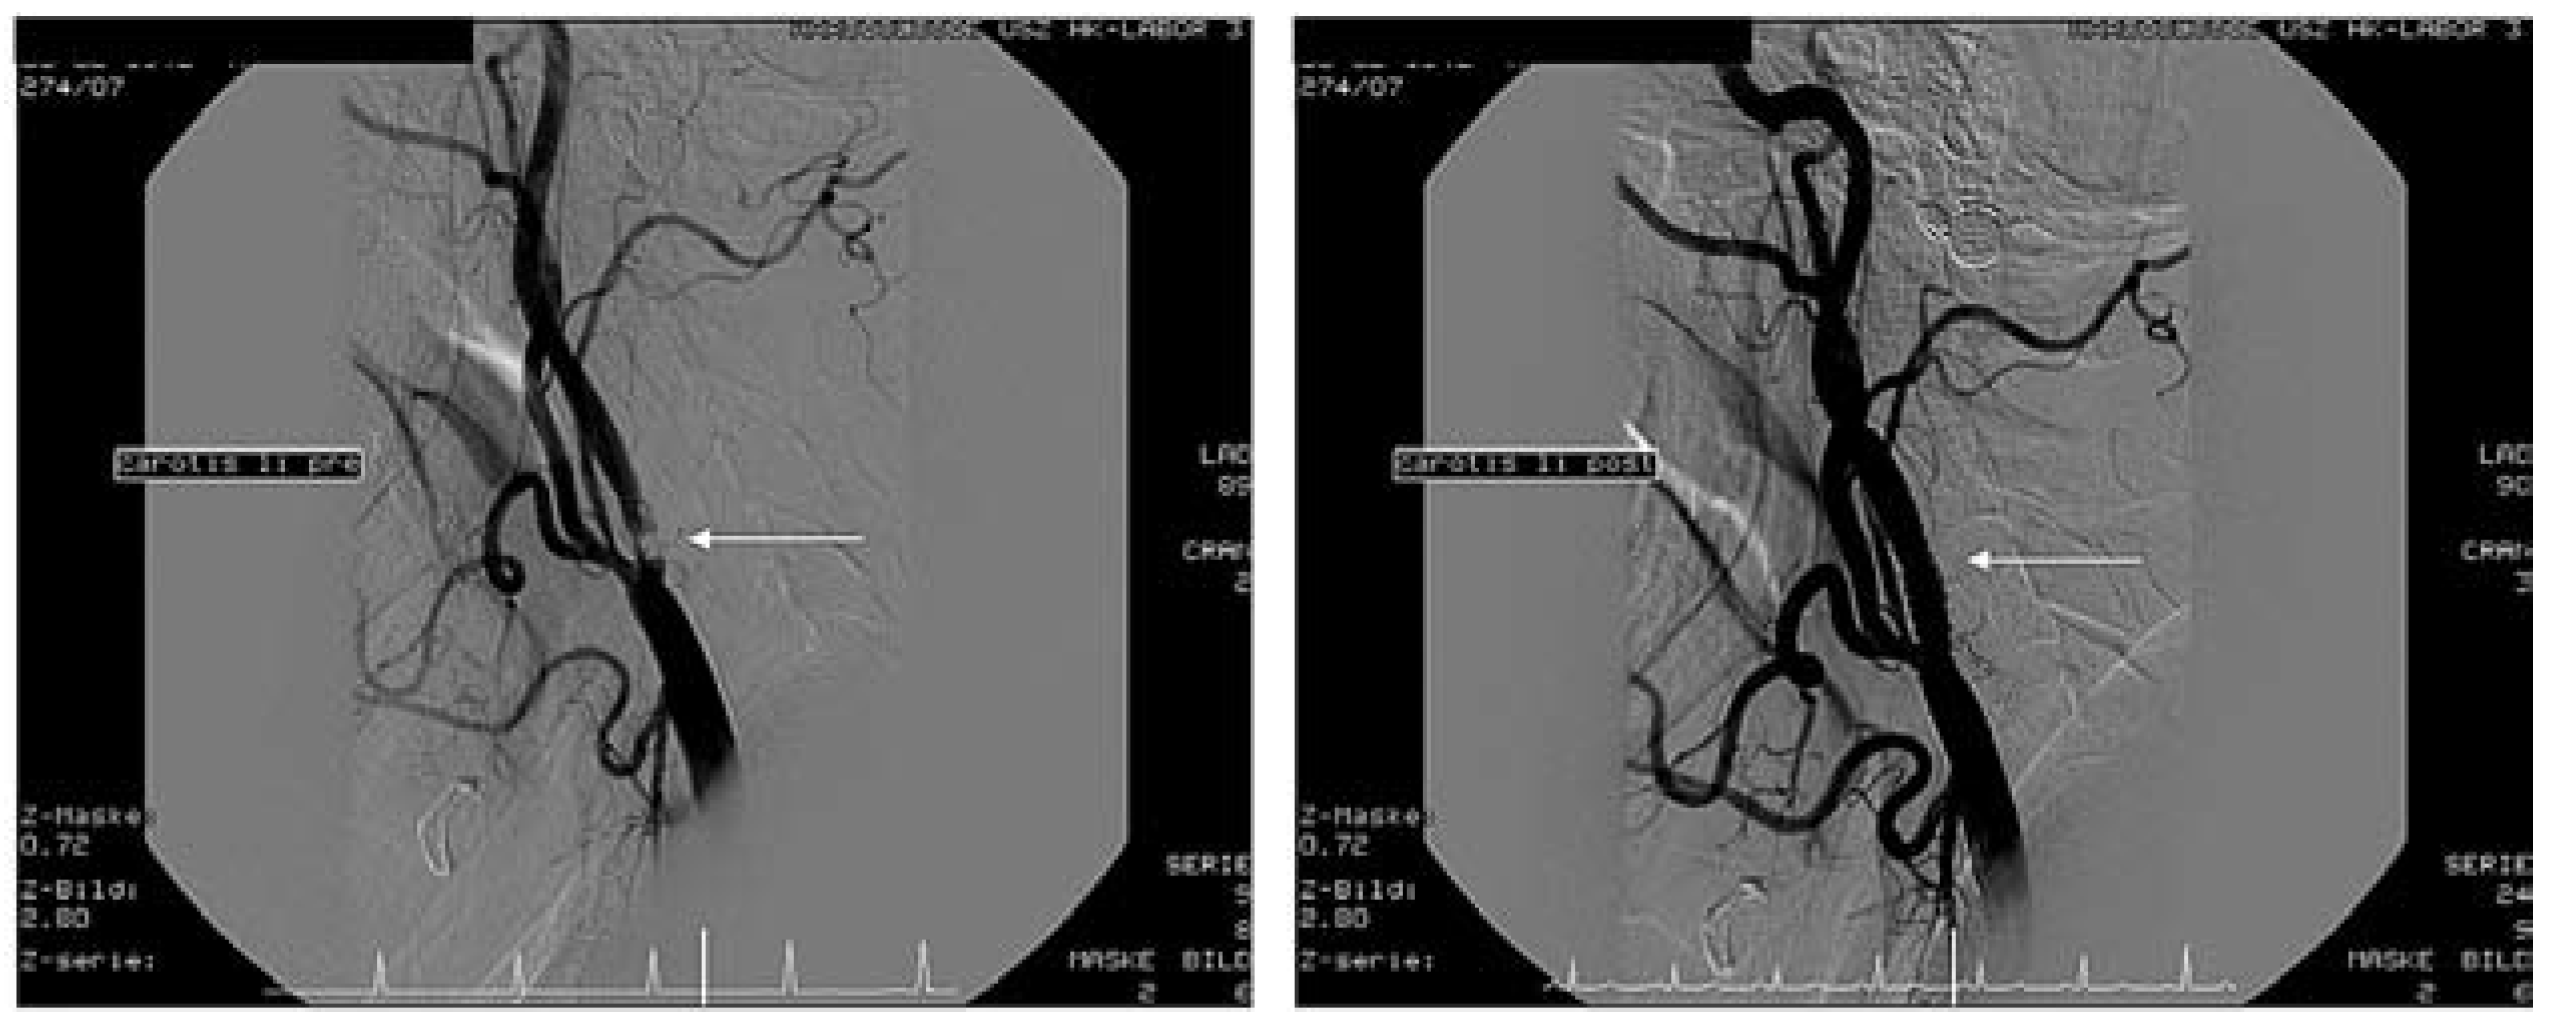

Figure 3. Stenose der Arteria Carotis interna unmittelbar nach der Bifurkation vor (links) und nach (rechts) Stenting.

Schliesslich entwickelte sich das Karotis-Stenting zu einem bedeutenden Eingriff für interventionelle Kardiologen. Neue Technologien besonders durch Verwendung von so genannten Filter-Devices zur Vermeidung von zerebrovaskulären Embolien aus rupturierten Plaques haben die Ergebnisse erheblich verbessert. Am UniversitätsSpital Zürich wurden in den letzten Jahren über 140 solche Eingriffe mit einer minimalen Komplikationsrate (30-Tage-Mortalität-, Herzinfarkt- und Schlaganfall-Risiko 2,1%) auch bei Hochrisikopatienten durchgeführt (Figure 3 and Figure 4). Diese Ergebnisse machen deutlich, dass sich das Karotis-Stenting heute zu einer Alternative der Karotis-Endarterektomie entwickelt hat.